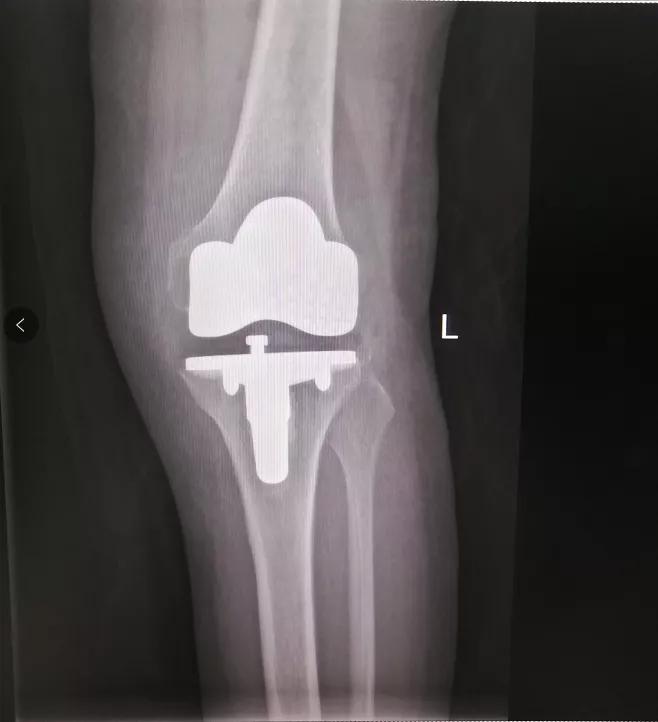

术前

术后

术后第一天

刘女士就能扶着助行器

下床活动了

术后一周便出院

打破了“伤筋动骨一百天”的说法